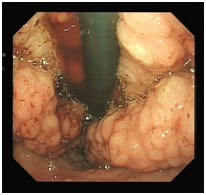

In this instance, a 53 year old Caucasian male with no significant past medical history presented to his primary care provider with a 2 week history of shortness of breath on exertion. Physical exam was unremarkable. Routine bloods revealed a Hemoglobin of 6 g/dL (13-17g/dL) with an MCV of 64 fL (80-100fL). Iron studies confirmed an iron deficiency anaemia. Other notable lab values included serum albumin 1.9 g/dL (3.5-5.0g/dL) with no proteinuria. CT Imaging of the thorax, abdomen and pelvis revealed a grossly dilated stomach, with diffuse circumferential wall thickening, measuring up to 3cm in maximum diameter (Figure 1). It also revealed extensive bilateral 2nd order pulmonary emboli and a large IVC clot extending from the level of the renal veins to the common iliac veins (Figure 2).

Figure 1CT image of grossly dilated stomach, with diffuse circumferential wall thickening.